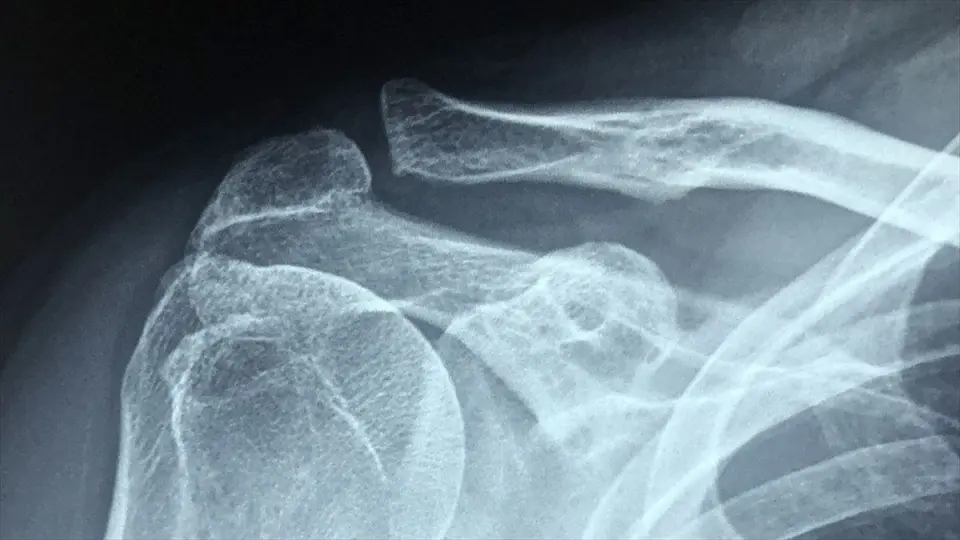

İSTANBUL (AA) - Sağlık Bilimleri Üniversitesi (SBÜ) Kanuni Sultan Süleyman Eğitim ve Araştırma Hastanesi Ortopedi ve Travmatoloji Kliniği Sorumlusu Prof. Dr. Cemil Ertürk, AA muhabirine, omuz ekleminin eşsiz bir anatomik yapısıyla vücudun en hareketli eklemi olduğunu söyledi.

Buna karşın, vücudun diğer eklemlerine göre bu eklemin sağlamlığının, kemik-kemik bağlantısından çok top ve yuva eklemini çevreleyen kapsül, tendon ve kas gibi yumuşak dokular tarafından sağlandığını ifade eden Ertürk, bu nedenle vücudun en hareketli eklemi olmasına karşın en fazla çıkma riskini de taşıyan eklem olduğunu söyledi.

Ertürk, omuzun çıkmasına engel olmak için eklemi çevreleyen yumuşak dokuların uyumlu çalışmasının son derecede önemli olduğunu, bu bölgede bir kere oluşan çıkığın daha sonra tekrarlama riskinin diğer eklemlere göre oldukça fazla olduğunu vurguladı.

İlk çıkığın 20 yaştan önce oluşması durumunda tekrarlama olasılığının yüzde 90 olduğunu belirten Ertürk, "Tekrarlayan omuz çıkıkları özellikle genç, aktif ve spor yapan genç hasta grubunda karşımıza çıkar ve 40 yaşından sonra nadiren görülür. İlk çıkık genellikle ciddi bir travma sonrası oluşur. Daha sonra özellikle 30 yaş altı hastalarda günlük aktiviteler sırasında çıkıklar oluşabilir. Çıkıkların tekrarlaması, hastanın korku duymasına, omuzunda çıkık endişesi yaşamasına ve günlük aktivitelerinde kısıtlama yapma ihtiyacı duymasına neden olabilir. Bu tip olgularda cerrahi tedavi gereklidir." diye konuştu.

"Günümüzde çıkık ilk kez oluyorsa, oturtulduktan sonra 1-2 hafta basit bir kol askısı sonrasında fizik tedavi önerilmektedir. Tekrarlayan çıkıklarda omuz tespiti sadece ağrı geçene kadar verilir. Tekrarlayan omuz çıkıklarında her çıkık sonrası omuz eklemindeki hasar fazlalaşabilmekte, kireçlenme ihtimali artabilmekte, tedavisi zorlaşabilmektedir. Tekrarlayan omuz çıkıklarında çoğunlukla artroskopik teknikler sayesinde, omuzun hareket açıklığı korunarak ağrısız, hareketli ve normal şartlarda yerinden çıkmayan bir omuz sağlanabilir. Özel aletlerle omuz artroskopisi ameliyatı gerçekleştirilerek, labrumdaki yırtılmış olan doku 4-5 milimetrelik vidalarla olması gereken yere sabitlenir. Artroskopik tedavisinin mümkün yöntemlerle tedavinin en önemli avantajı, yara bakımını gerektirmemesi, doku iyileşmesinin daha hızlı olması ve hasta konforudur."

Artroskopik tedavinin uygulanamadığı hastalarda yırtık olan labrumun, açık tekniklerle yerine dikilebileceğini ifade eden Ertürk, kemik lezyonlarının eklenmesinin, cerrahi tedavi yöntemlerinin değişmesine neden olabildiğinden açık cerrahilerin gerekebileceğini anlattı.